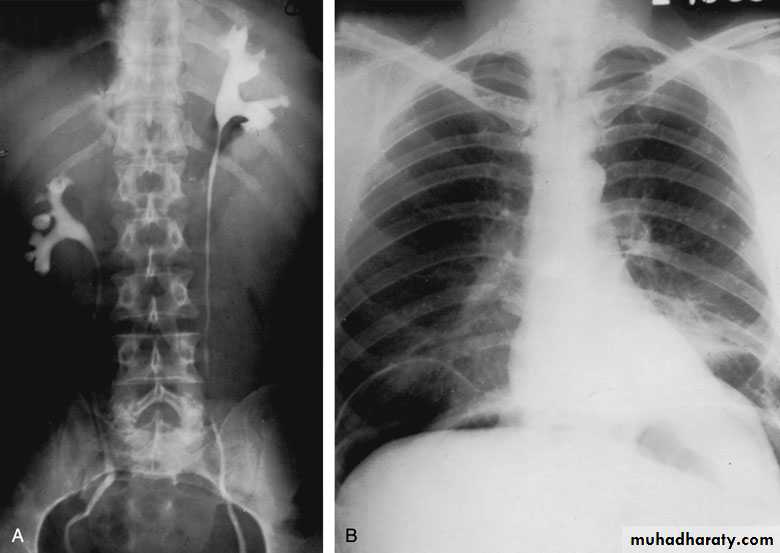

Postcaval (Retrocaval) ureter (Preureteral Vena Cava )

The right ureter pass behind the inferior vena cavaThis might causes obstruction

It is a vascular abnormality

Incidence: about 1 in 1500

Although it is congenital, most patients present at 3rd or 4th decade.

Diagnosis: IVU

Treatment

surgical correction involves ureteral division, with relocation and ureteroureteral or ureteropelvic reanastomosis, usually with excision or bypass of the retrocaval segment, which can be aperistaltic